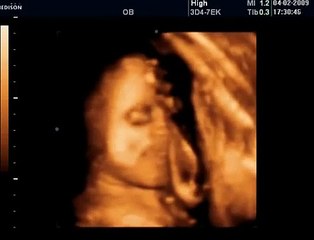

HAFTA HAFTA Gebelik Takibi deneyimli kadın doğum uzmanı Op. Dr. Fatih Esen'in videolu anlatımıyla Bebek.Tv'de: br br br 21 Haftalık Gebelik: br br Deneyimli kadın doğum uzmanı Op. Dr. Fatih Esen anne-baba adaylarına gebeliğin 21. haftasında anne adayı ve bebekte neler yaşandığını anlatıyor, önemli hatırlatma ve tavsiyelerde bulunuyor. br br Bu video Hafta Hafta Gebelik kapsamında Bebek.Tv tarafından hazırlanmıştır. br br Gebelik-doğum-bebek gelişimi videoları Bebek.Tv'de: br Bebek videoları: br Hamilelikte beslenme: br Kaç haftalık hamileyim, kaç aylık hamileyim? br Hamilelikte öksürük bebeğe zarar verir mi? br br Bebek.